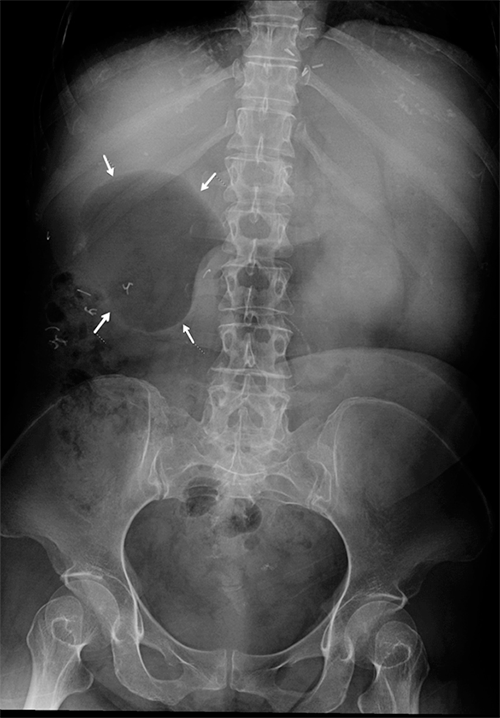

A decision was made to pexy the efferent anastomotic limb further along the greater curve of the stomach and to an adjacent portion of jejunum immediately beyond to prevent future intussusception episodes (Figure 5). The efferent limb pexy was created with a gentle curve in mind to avoid possible kinking or obstruction at its apex. Postoperative GI contrast studies and a CT scan confirmed normal transit through this area (Figure 6). Postoperatively, the patient did well and recovered to discharge several days later.

Figure 6. Postoperative Upper Gastrointestinal Series and CT. Published with Permission

Image demonstrates persistently dilated and air-filled duodenal bulb in right upper quadrant and right-sided small bowel opacification with contrast.